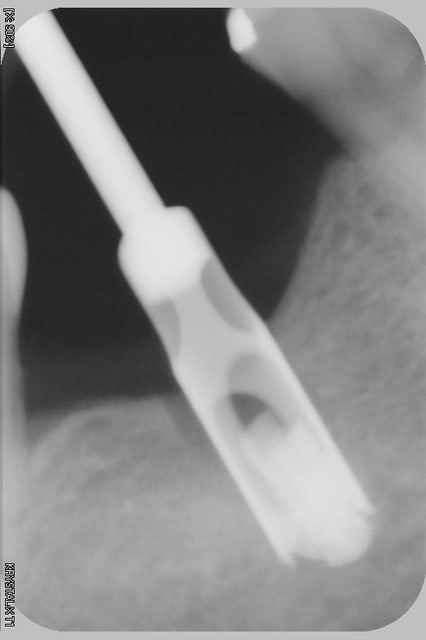

l'irrigation interne moi je n'en veux plus...c'est un nid à merde in-nettoyable correctement, et quelque part au patient suivant, tu lui ré-injectes toute ce bouillon de culture directement dans l'os....

çà t'évite peut être quelques problèmes d'échauffement...mais pas vraiment les infectieux...

çà me fait penser...irrigation interne...Zimmer??? (il me semble une des dernières marques à proposer ce genre de forets...qui coûtent la peau du cul, donc on les garde jusqu'au bout...pas bon, car un foret qui ne coupe plus, çà chauffe fort...il vaut mieux un foret classique qui coupe bien utilisé à basse vitesse...)

Pour l'irrigation interne, je n'en parlerai même pas tellement le concept me semble dépassé.

Juste pour le plaisir, après stérilisation passe un fil métal dans ton foret et confirme que tu ne trouve que le fil à la sortie...